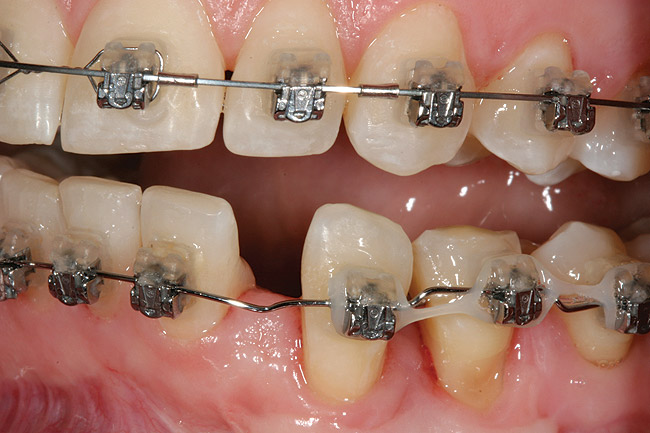

This treatment plan was elected with the premise to reevaluate treatment options during orthodontic tooth movement. Soft-tissue augmentation was initiated to correct the mucogingival defect in the area of teeth Nos. 21 and 22. A free gingival graft was performed to achieve an adequate band of attached and keratinized gingiva to resist potential stripping on the root surfaces of teeth Nos. 22 and 21 during orthodontic movement (Figure 8). Orthodontic movement then was initiated to site-develop position No. 23 for an implant (Figure 9 through Figure 11). Orthodontics also was used to idealize the patient’s occlusion and develop canine guidance to minimize occlusal load and maximize the redistribution of forces36-40 for protecting the future implant from deleterious forces. The space was opened around the peg lateral tooth No. 7, and the gingival levels were aligned for maxillary incisors. Bonding was performed to restore the length of teeth Nos. 8 through 10 and to bond the peg lateral to a normal tooth form, which allows the orthodontist to idealize the posterior occlusal scene and maintain canine guidance (Figure 12 through Figure 13).

Figure 12  Right buccal view showing posterior occlusion established, canine guidance and proper space appropriation around peg lateral tooth No. 7, and intruded worn incisors.

Figure 12